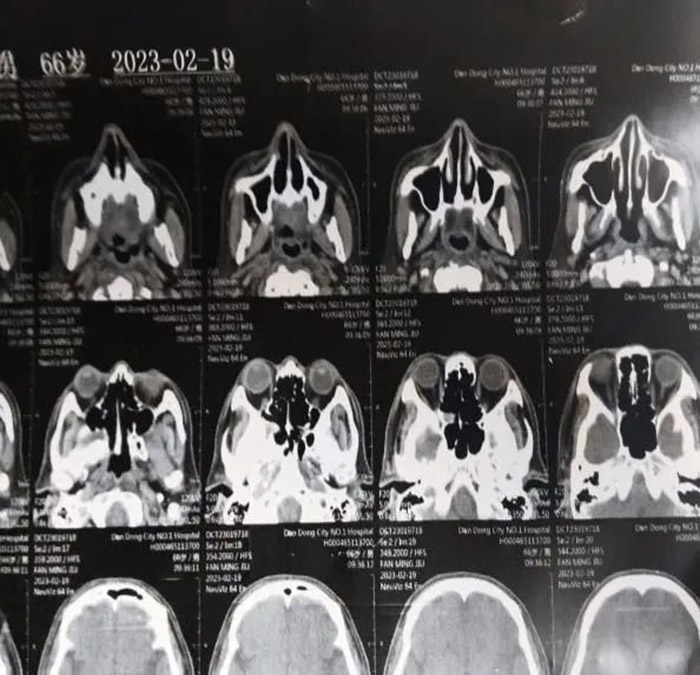

罹患肿瘤 初战告捷 68岁的范先生,于2014年1月27日因鼻腔流血、鼻塞、鼻腔分泌物有异味等症状,来到我院耳鼻喉科就诊。经鼻咽部CT扫描,发现鼻咽占位。在完成肿瘤部分摘除术后,转入我院放疗科,进一步做鼻咽癌放疗根治术。

经过一个疗程的放射治疗后,范先生的病情达到了临床预期的效果,原有症状明显改善或消失,一个月后CT复查效果提示,鼻咽癌残余肿瘤放疗后明显缩小,病情稳定好转 。

2021年7月,这是患病的第七年,范先生发现自己的右眼逐渐视物不清,原以为只是年龄的问题老花眼或眼疲劳。但是从眼球逐渐外凸后,他开始紧张起来。在家人的陪伴下,范先生来到我院检查病情。鼻咽部CT显示:鼻咽癌复发,PET/CT结果显示:筛窦蝶窦有浸润、鼻腔转移、眼球外凸系肿瘤变大外张导致。

经过专家组研究,制定了二次放疗的方案,并对放射治疗过程进行分期评估和监控,以便进行方案修改与调整。这次治疗采用了先进的TaiChiPro双模式放射治疗系统。随着治疗次数的增加,范先生明显感觉自己的症状逐渐减轻。接近一个疗程的时候,他的视力已经恢复了很多,眼球外凸也明显回缩,除味觉稍差,其它的症状都没有出现。出院后一个月复查,CT提示鼻咽癌及转移灶明显改善,眼球外凸症状消失。

二次放疗后的CT图像和右眼恢复情况